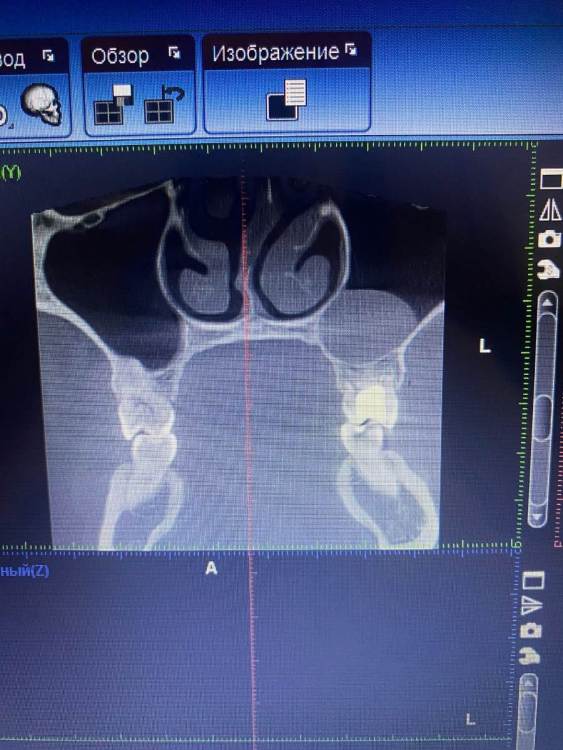

АлинаЯга Опубликовано 14 июня, 2022 Автор Поделиться Опубликовано 14 июня, 2022 @red_butler сделала сегодня кт . Киста такая огромная? Ссылка на комментарий